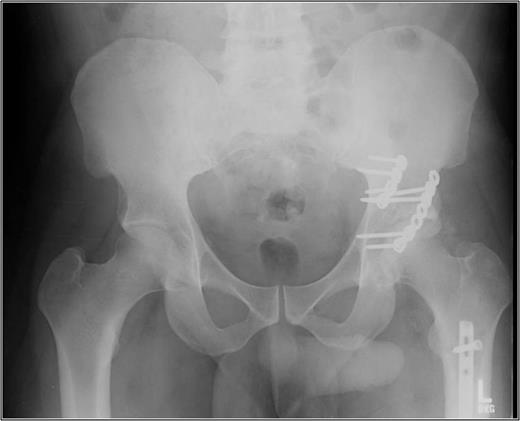

Operative management focused on closed reduction of the dislocated left hip. Two 5.0 mm Schanz pins with a carbon fiber bar (Zimmer, Warsaw, Indiana, USA) were placed in the proximal femur fragment. This was used to aid with the closed reduction maneuver of knee flexion, hip traction, adduction and internal rotation. Confirmed by intra-operative fluoroscopy, the femoral head was irreducible due to the engaging femoral head lesion on the acetabulum. A conversion to open reduction via a Kocher–Langenbeck approach in the lateral position ensued. The femoral head and posterior wall were reduced under direct visualization with two 3.5 mm pelvic reconstruction plates (Zimmer). The patient was moved to the supine position and underwent definitive femoral fixation with a retrograde, reamed femoral nail (Zimmer). Thigh compartments at the conclusion of the femoral fixation were tense and non-compressible, requiring a thigh compartment fasciotomy. Negative pressure therapy was placed over the incision and the knee laceration was primarily closed. After multiple washouts of his lateral fasciotomy incision, he was primarily closed 1 week after initial presentation. He was discharged non-weight bearing on his left lower extremity on post-operative day 22. Eleven months post-injury, he remains full weight bearing without assistance. He reports intermittent pain with ambulation and radiographs show early arthritic changes and heterotopic ossification of his left hip (Fig. 4).

AP pelvis 8 months status post-ORIF of posterior wall with retrograde femoral nail. The left hip demonstrates early post traumatic arthritis and heterotopic ossification.